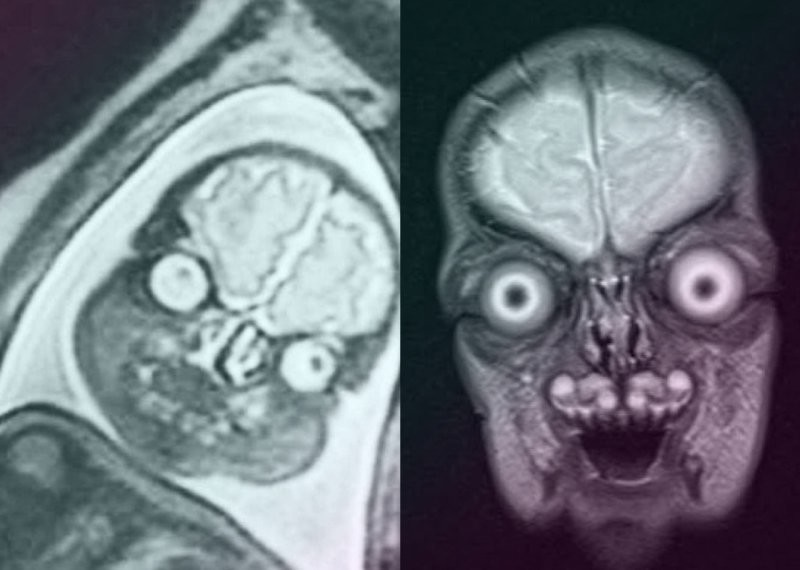

Марс атакует!

Он даже улыбается!

А для мамы всё равно самые красивые!